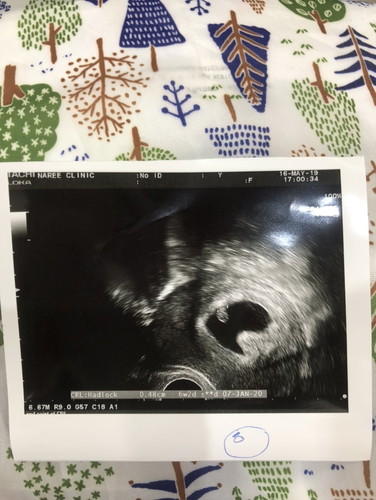

ถุงตั้งครรภ์ไม่กลม มีผลต่อการตั้งครรภ์มั้ยคะ

แม่ท่านไหน us แล้วเจอถุงตั้งครรภ์ไม่กลมสวยบ้างมั้ยคะ แล้วจะมีผลอะไรต่อการตั้งครรภ์มั้ยคะ แอบกังวล เนื่องจากท้องจากทำ ivf คะ

น่าจะเป็นมุมกล้องหรือเปล่าคะ อันนี้ไม่แน่ใจ ของเราถุงตั้งครรภ์ก็ไม่ได้สวยอะไร แต่น้องก็ปกติดีทุกอย่างค่ะ

ไม่น่าจะเป็นอะไรนะคะ อาจจะมีลำไส้หรือกระเพาะแม่ไปเบียดถุงตั้งครรภ์อะคะ